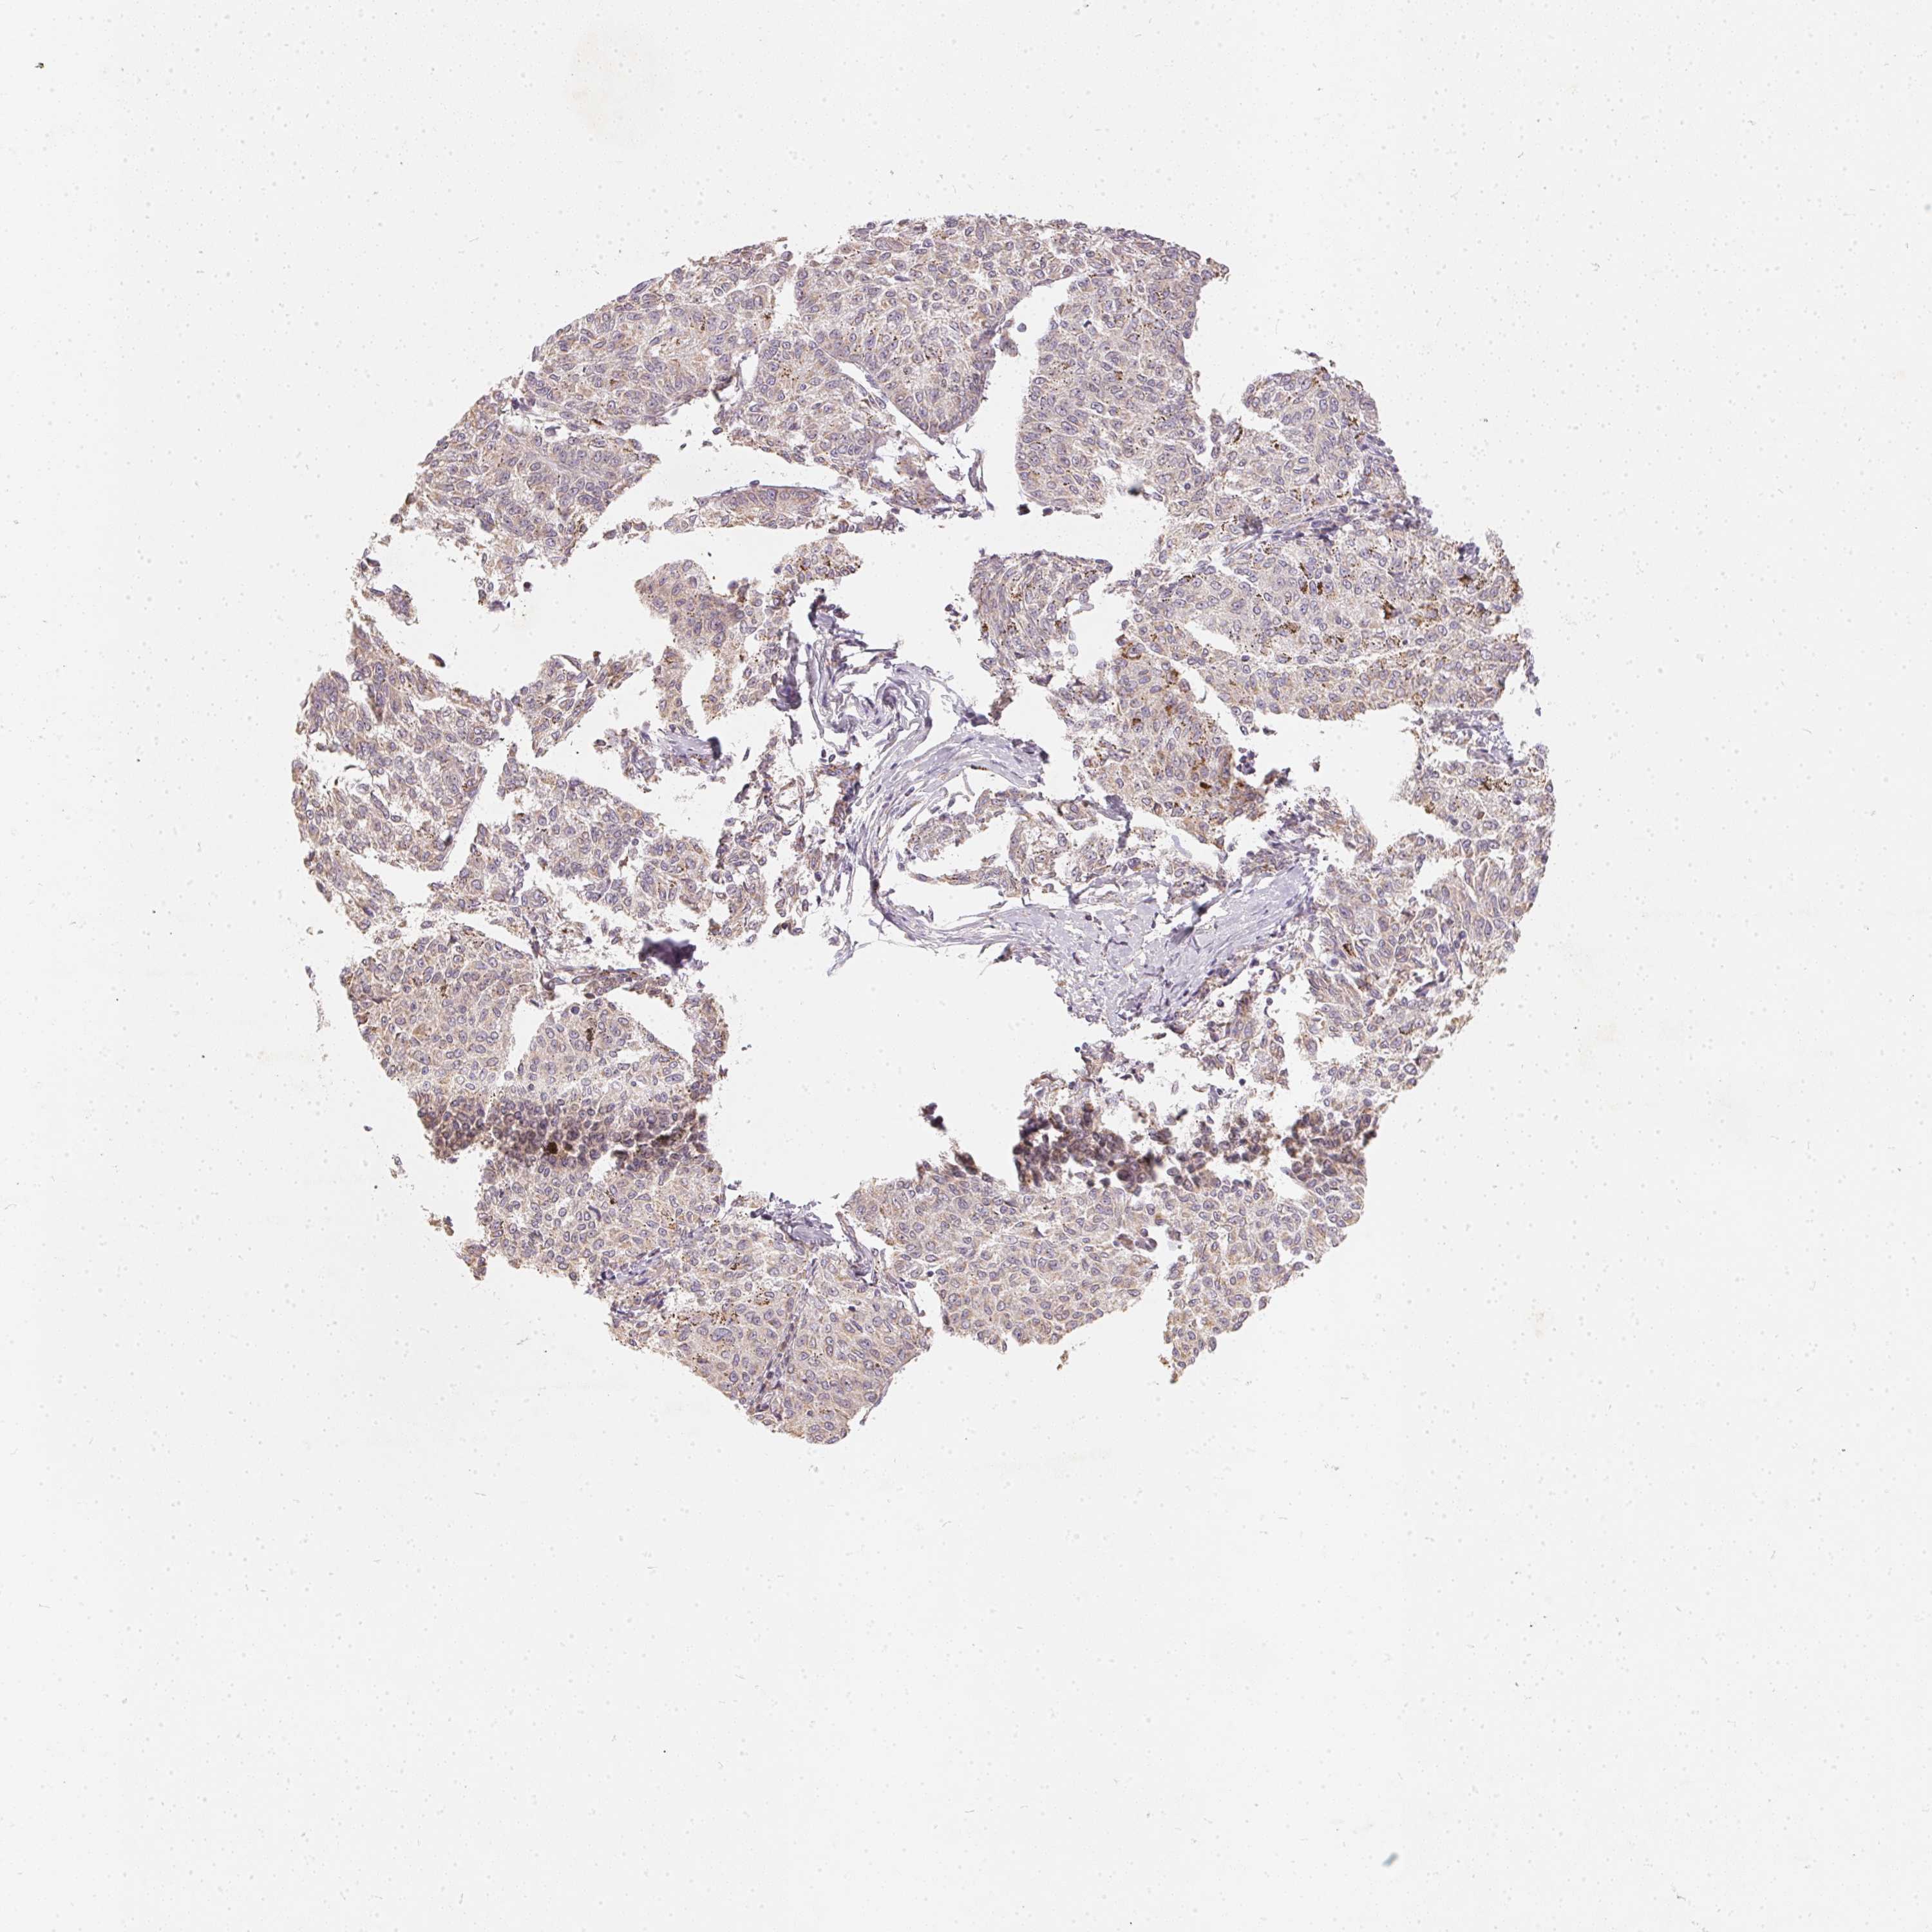

MELANOMA - Protein expressioni

A mouse-over function shows sample information and annotation data. Click on an image to view it in a full screen mode. Samples can be filtered based on level of antibody staining by selecting one or several of the following categories: high, medium, low and not detected. The assay and annotation is described here.

Antibody staining in the annotated cell types in the current human tissue is reported as not detected, low, medium, or high, based on conventional immunohistochemistry profiling in selected tissues. This score is based on the combination of the staining intensity and fraction of stained cells.

Each image is clickable and will lead to virtual microscopy that enables deeper exploration of all samples and also displays staining intensity scores, fraction scores and subcellular localization as well as patient and tissue information for each sample.

Antibody HPA036823

Antibody HPA036824

Antibody HPA061412

Malignant melanoma, NOS

Malignant melanoma, Metastatic site